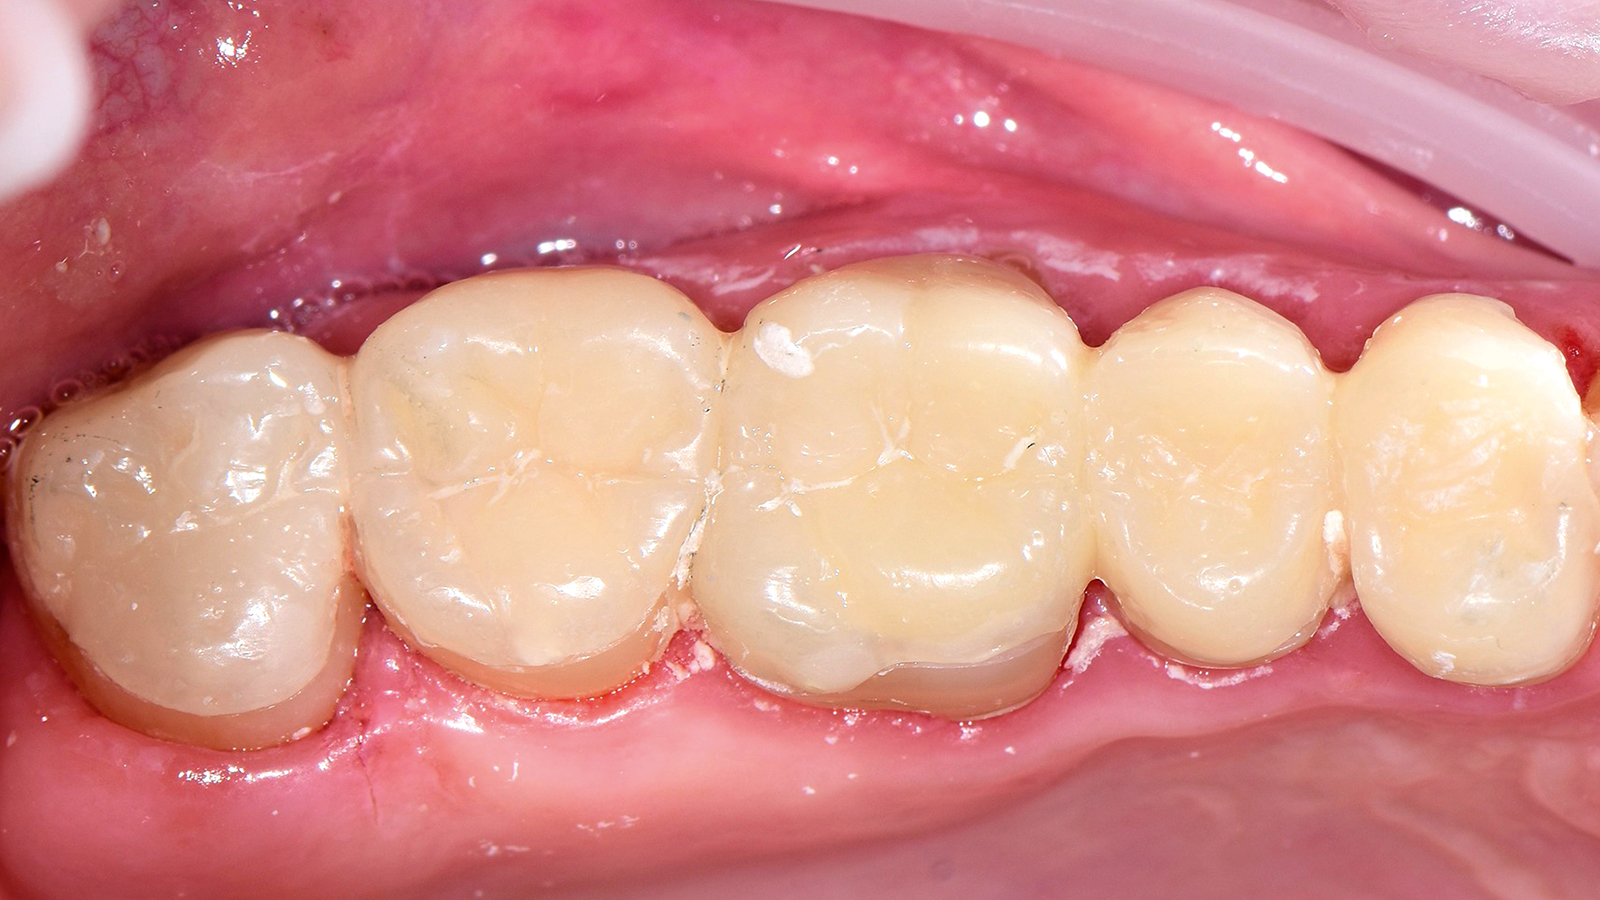

A high-viscous composite such as Charisma Diamond or Charisma Topaz can be used as capping layer if preferred. This allows the creation of the natural morphology in the occlusion which is requested e.g. in case of big cavities or cusp replacement. Any shade can basically be used based on individual preferences. Especially the Charisma Diamond/ Charisma Topaz ONE Shade promises the same colour adaptation to the surrounding dentition like Charisma Bulk Flow ONE.

The ONE shade has been optimised to deliver the perfect balance of chroma and translucency that allows the restoration to become virtually invisible. Therefore, the ONE shade can be used with confidence in any Class I and Class II restoration. And this colour adaptation is what we call Adaptive Light Matching.

Charisma Bulk Flow ONE is a flowable bulk-filling composite with curing depths of up to 4mm whereas the high-viscous composites Charisma Classic as well as Charisma Diamond and Charisma Topaz in ONE Shade are applied in incremental layering techniques in 2mm. The different viscosities and application techniques imply different benefits complementing eachother in everyday posterior restorations.